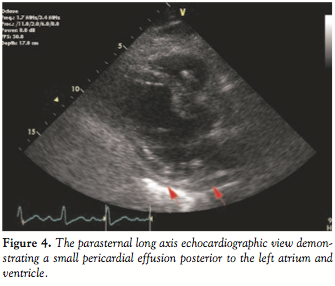

Two overlapping 3.0 x 12 mm Jomed covered stent grafts (Jomed International AB, Helsingborg, Sweden) were deployed over the affected site and subsequent angiography showed TIMI 3 flow with no further extravasation or distal plaque embolization (Figure 3). Bedside echocardiogram revealed a small pericardial effusion posterior to the left atrium and ventricle and no significant fluid around the right ventricle, while the right atrium was not well visualized (Figure 4). Right heart catheterization showed normal right-sided pressures without equalization of diastolic pressures.